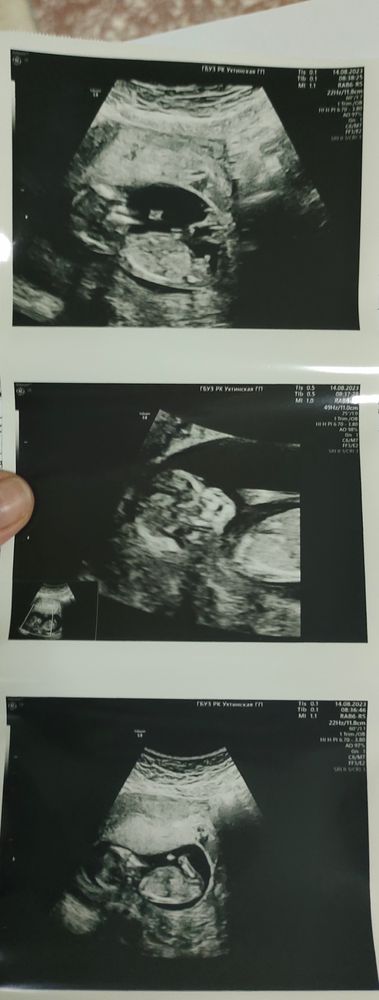

мальчик или девочка?

Здравствуйте, девушки! Часто вижу тут посты в последнее время про определение пола по фото с первого скрининга... Я сама вижу вроде как мальчика, а вы?) Спасибо всем за мнение!